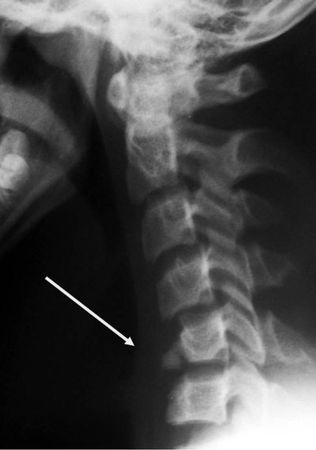

Рис. 4.4. Истинный травматический передний вывих CII у ребенка 16 лет. Линия Swischuk не нарушена (дуга CII не сломана). Имеется разобщение суставных поверхностей CII–CIII. Смещение CII кпереди и вниз на Vi тела CIII